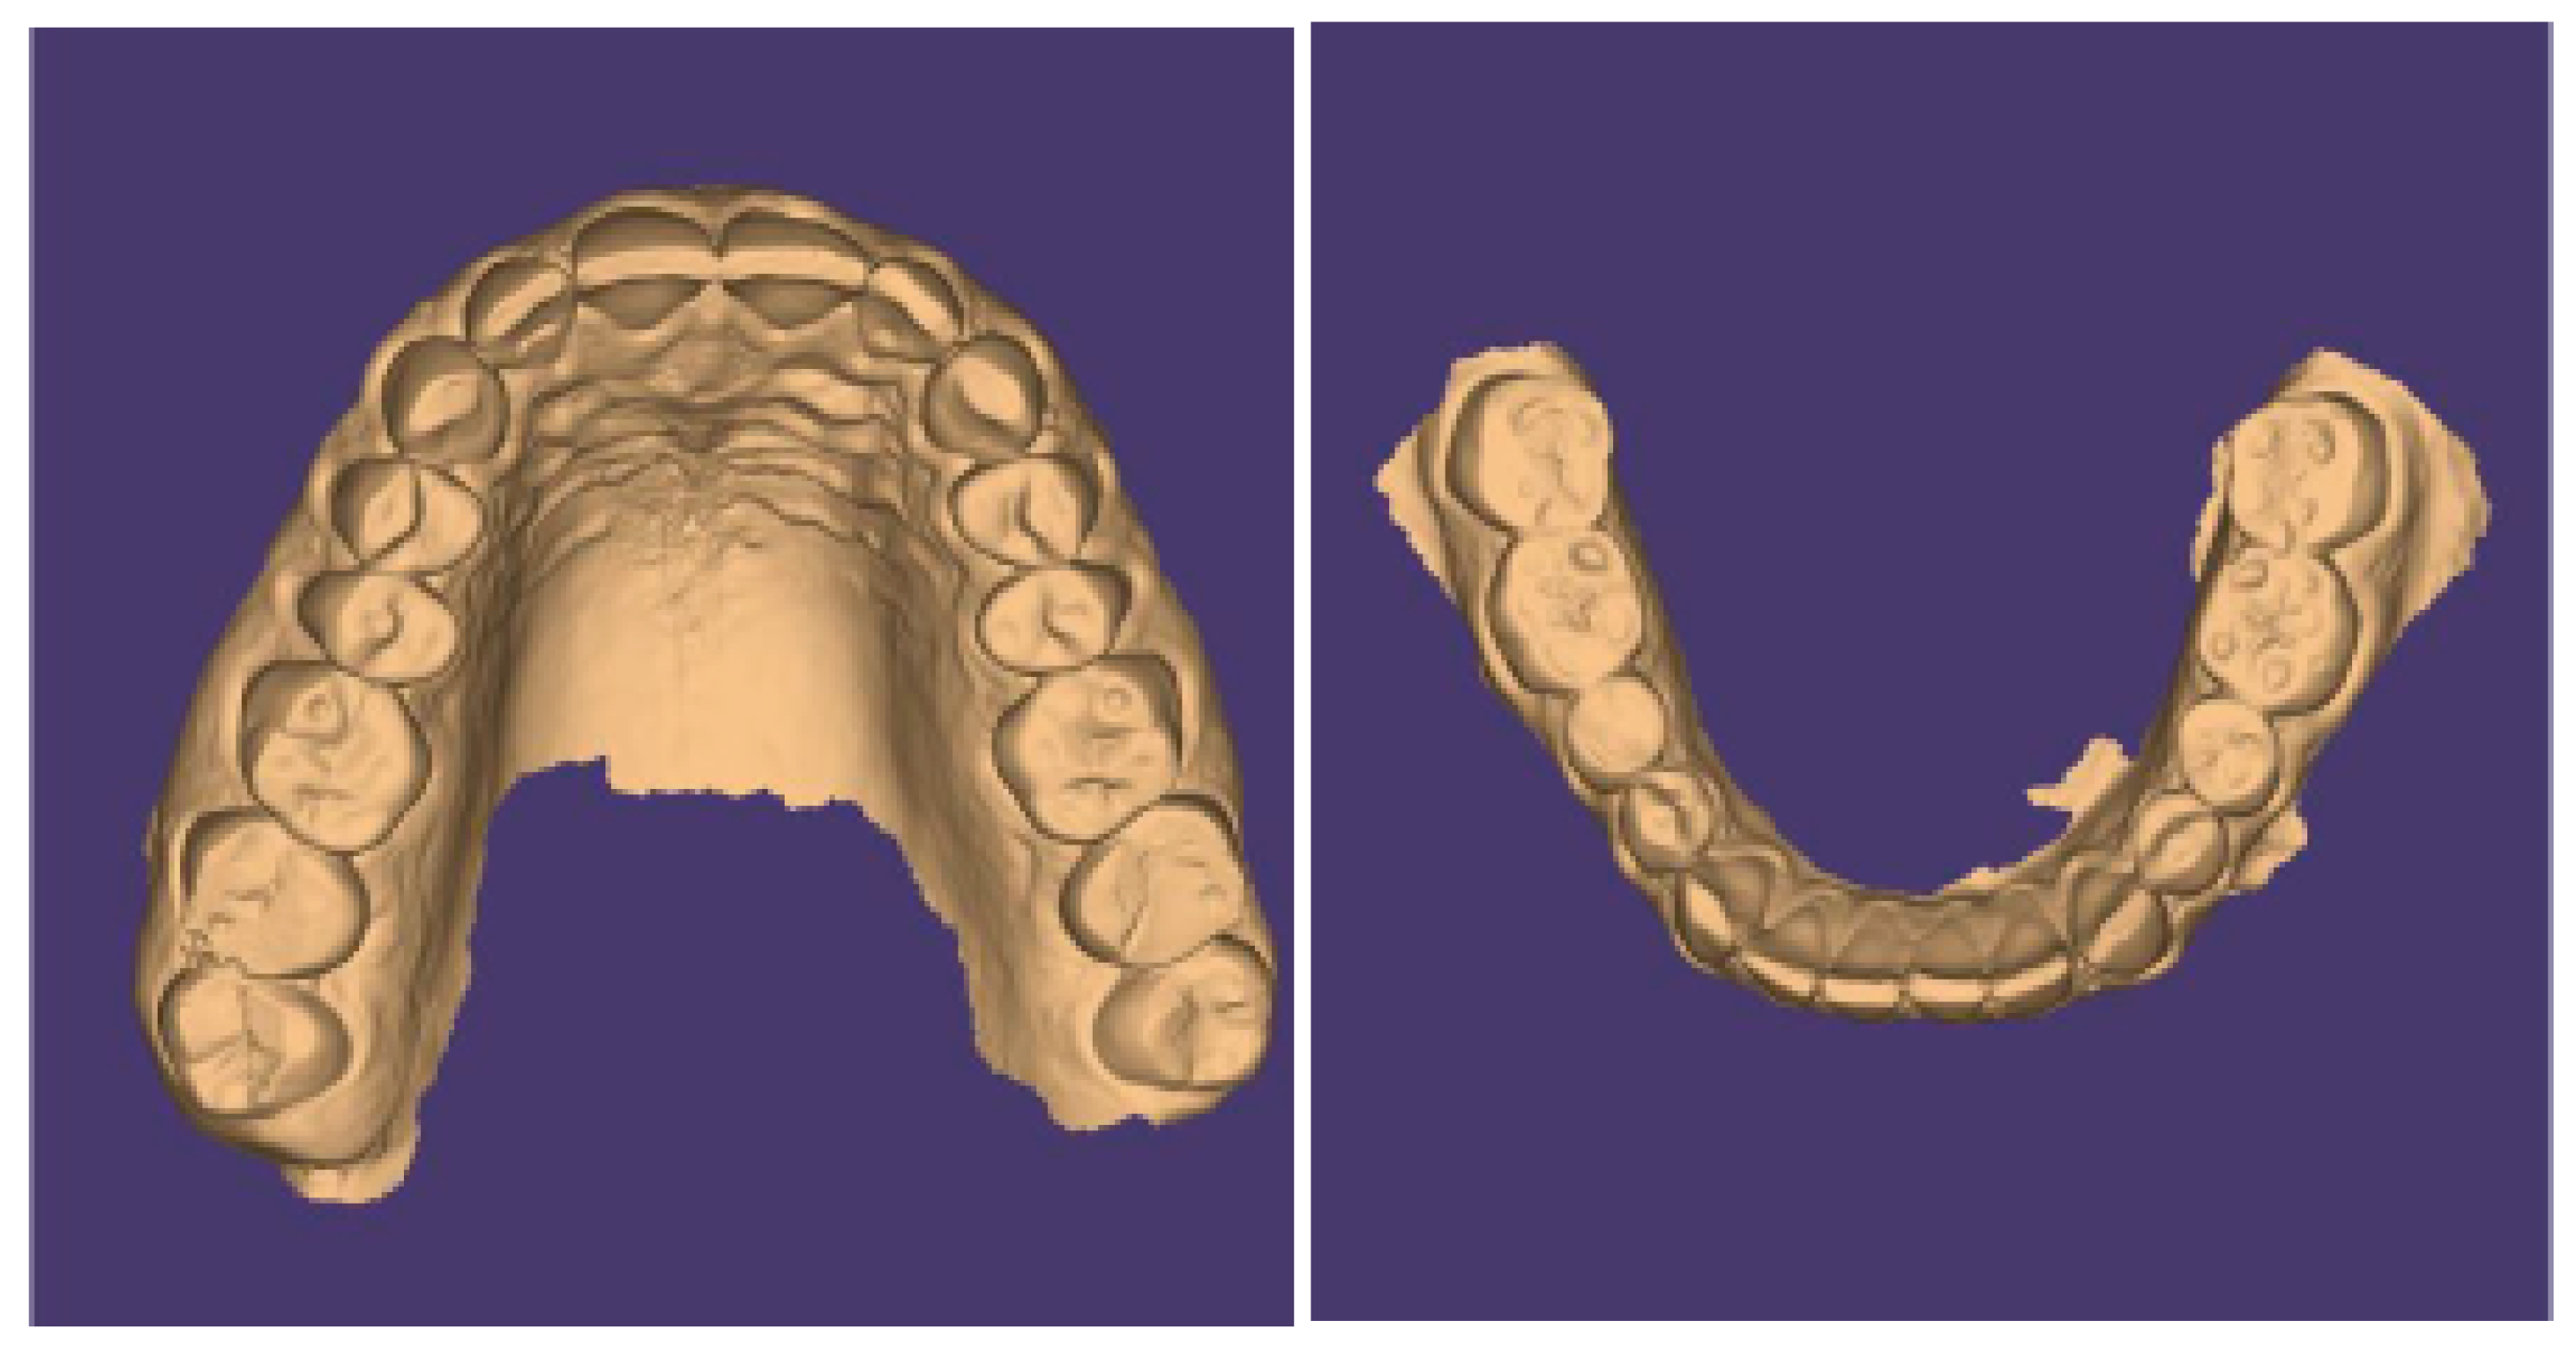

Intraoral views are shown in Figure 25, and Figure 26 reports orthopantomography: the absence of element 26, implant-prosthesis of element 31, and condylar asymmetry. It was indicated to investigate the diagnostic with an X-ray of elements 3.6 and 4.6.

Figure 26. Absence of element 26, implant-prosthesis of element 31, and condylar asymmetry. It was indicated to investigate the diagnostic with an X-ray of elements 36 and 46.